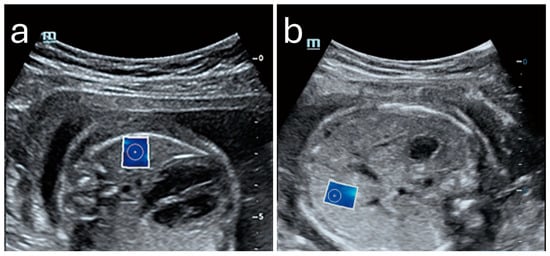

Sonoelastography offers a unique window into fetal development by providing quantitative insights into tissue properties and markers for identifying developmental progress and complications. By measuring the elastic properties of key organs such as the lungs, liver, and brain, clinicians could potentially evaluate organ maturity, detect potential anomalies, and make informed decisions regarding perinatal care [,,,,,,,,]. Figure 4 shows an example of a normal lung and liver in a fetus.

Figure 4. Normal shear wave elastography images of fetal lung (a) and liver (b) with elasticity values of 4.43 kPa and 5.09 kPa, respectively. Image adapted from Liu et al. [] under a Creative Commons Attribution 4.0 International License. Changes were made to resize and adjust the images.